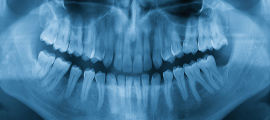

CT検査によって取得した口腔内の3Dデータから、歯の位置や埋伏歯(歯冠の全てまたは一部が埋まって出ていない歯)・過剰歯(決まった本数よりも多く生えている歯)などを確認します。

これらを事前に確認しておくことで、歯が移動する際に邪魔になってしまうのを防ぎます。また、歯の移動に大きく関係する骨の厚さなどの情報も得られ、精度の高い矯正治療のために不可欠な検査です。

レントゲン撮影や歯科用CTなどの精密検査を行い、その診断結果から患者さん一人ひとりに合わせた治療計画をご提案させていただきます。また、口腔内スキャナー(iTero)で採取したデータをもとに現在の歯並びから矯正終了までの精密なシミュレーションをいたします。

パノラマレントゲン